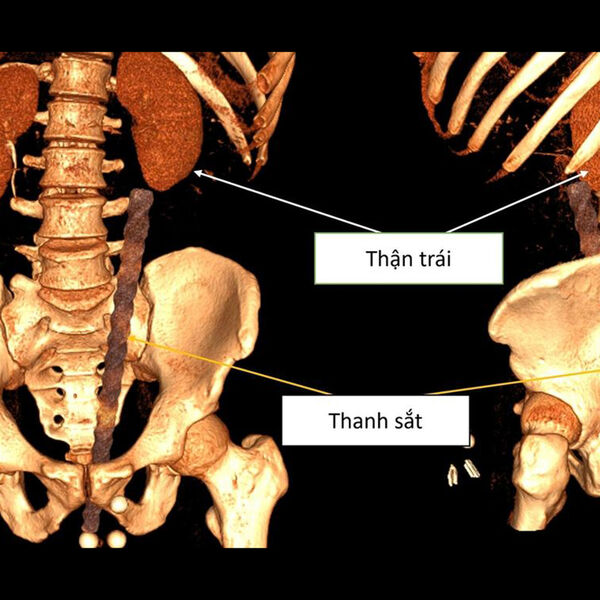

Во вьетнамской провинции Куангнинь 38-летний мужчина был срочно доставлен в больницу после серьезной травмы — металлический строительный прут проник в его тело примерно на 30 сантиметров после неудачного падения, пишет Daily Star.

Обследование показало, что арматура вошла через анальное отверстие мужчины и повредила несколько внутренних органов. По данным врачей, металлический прут вызвал сильное кровотечение в анальном канале, мочевом пузыре и брюшной полости. Также были зафиксированы повреждения органов таза.

Во время операции медики обнаружили, что объект находится опасно близко к поясничной области пациента. У мужчины диагностировали ушиб передней стенки прямой кишки длиной около 3 см, повреждение левого мочеточника, разрыв возле почечной лоханки, а также разрыв стенки левой подвздошной артерии, что привело к сильному внутреннему кровотечению и образованию крупной гематомы.